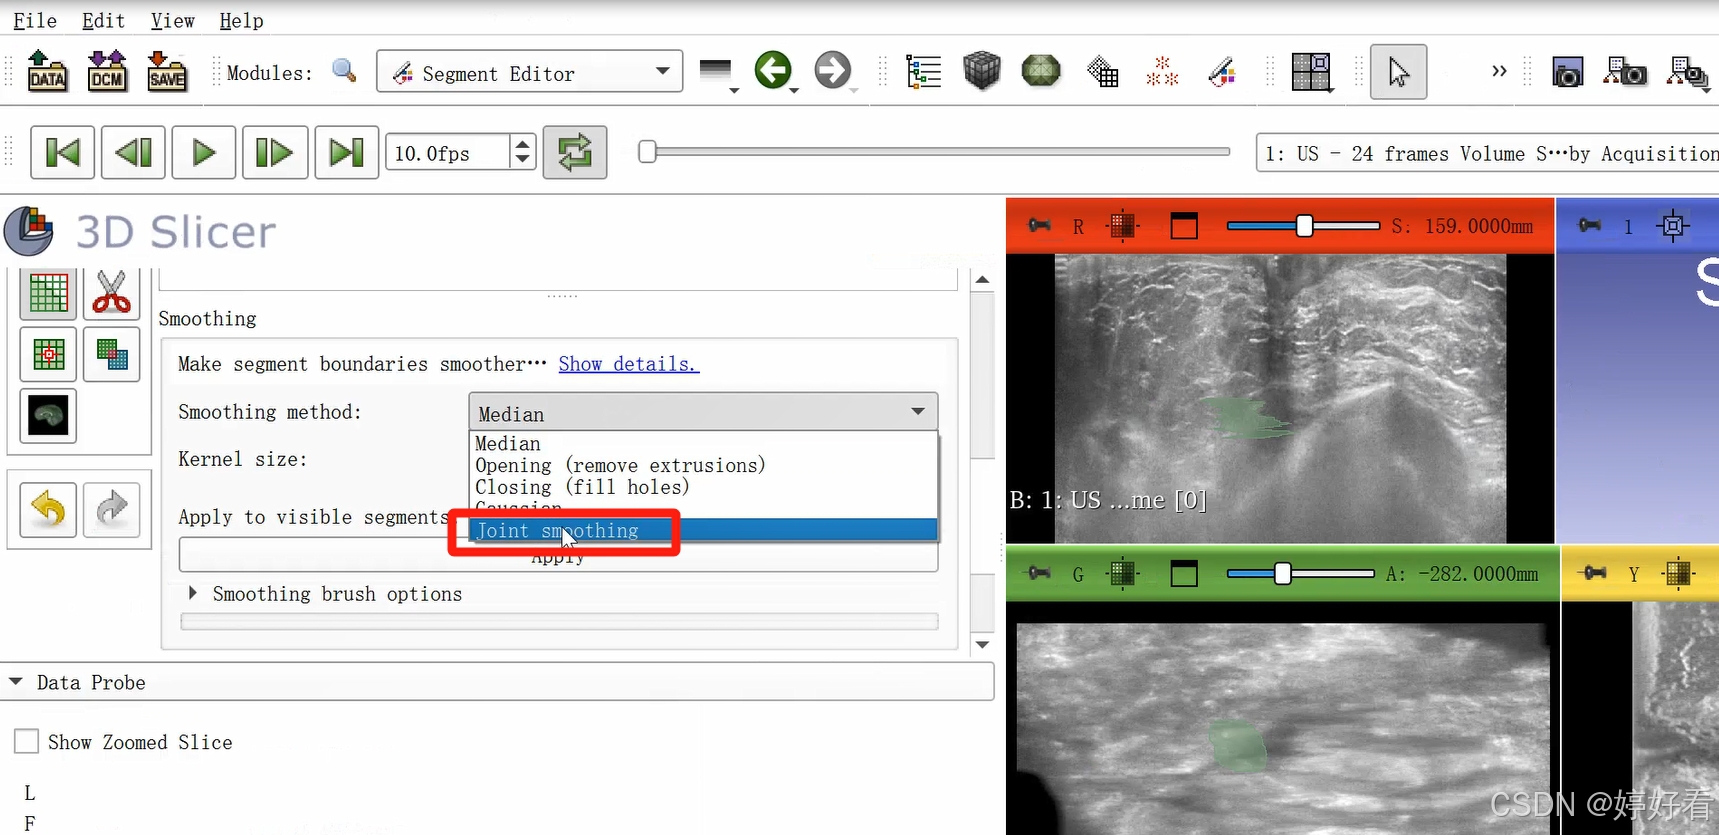

2.7 Smoothing功能使图像表面更光滑

首先,选中Smoothing功能,然后选择Joint smoothing,最后点击Apply。